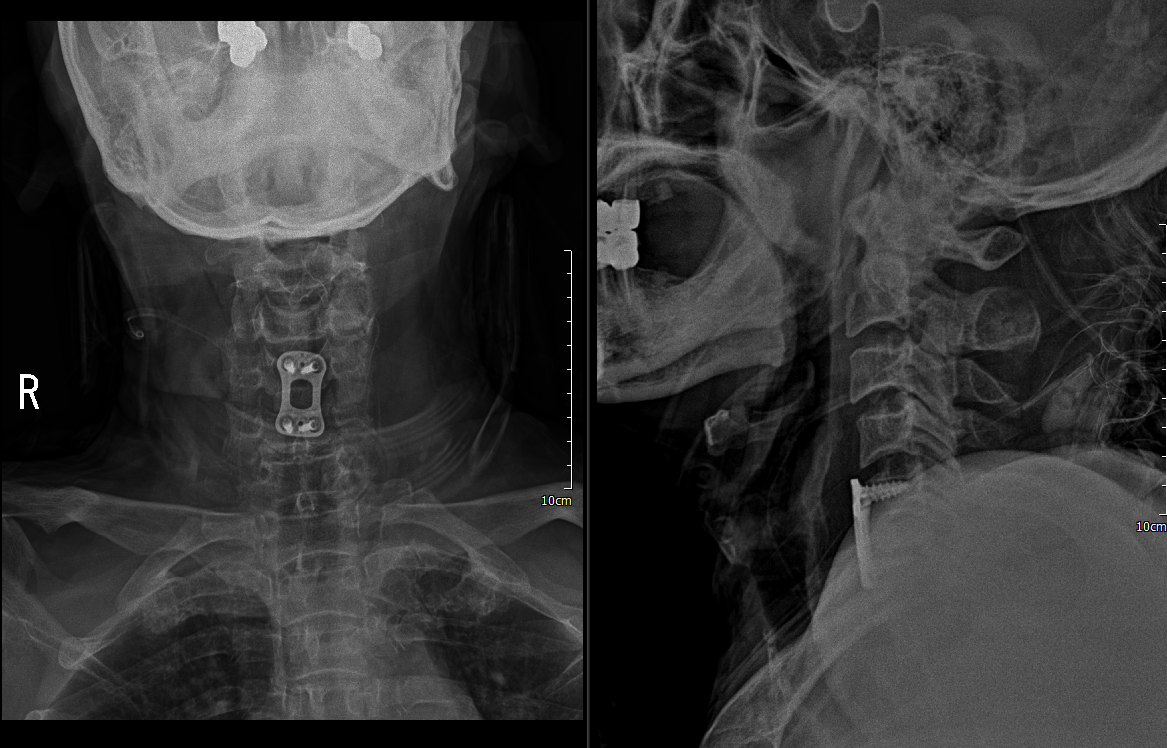

1. C5/6 ACDF & iliac bone graft(Rt)

2. PF C5/6

자동차 보험 환자라 cage 및 plate를 둘다 사용할 수 없어서 cage 대신에 우측 iliac bone을 떼서 C5/6 discectomy 이후 넣음

C5/6 ACDF & iliac bone graft(Rt)

하지만 안정성 확보를 위해 5일 후 뒤쪽으로 고정술 시행

lateral mass screw을 사용하여 고정술 시행